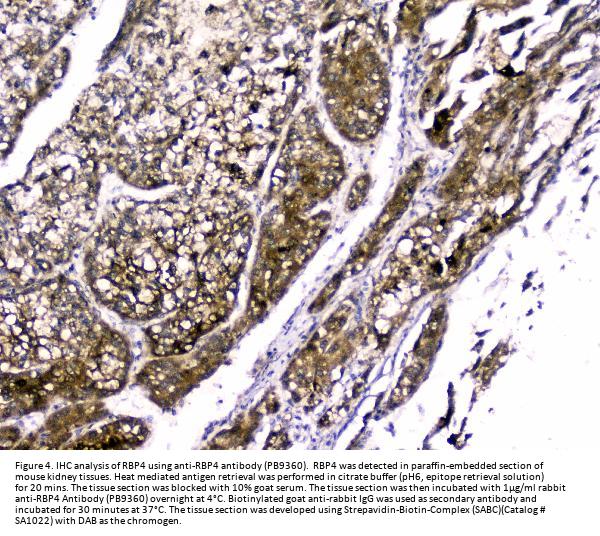

Immunohistochemistry (Paraffin-embedded Section), 2-5μg/ml, Human

RBP4 is also known as RDCCAS. This protein belongs to the lipocalin family and is the specific carrier for retinol (vitamin A alcohol) in the blood. It delivers retinol from the liver stores to the peripheral tissues. In plasma, the RBP-retinol complex interacts with transthyretin which prevents its loss by filtration through the kidney glomeruli. A deficiency of vitamin A blocks secretion of the binding protein posttranslationally and results in defective delivery and supply to the epidermal cells.

E.coli-derived human RBP4 recombinant protein (Position: E19-201L). Human RBP4 shares 86% amino acid (aa) sequence identity with both mouse and rat RBP4.

Boster Bio Anti-RBP4 Antibody Picoband® catalog # PB9360. Tested in ELISA, IF, IHC, WB applications. This antibody reacts with Human. The brand Picoband indicates this is a premium antibody that guarantees superior quality, high affinity, and strong signals with minimal background in Western blot applications. Only our best-performing antibodies are designated as Picoband, ensuring unmatched performance.